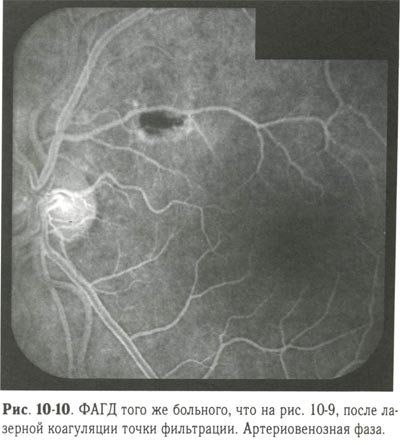

Перед лазерной коагуляцией необходимо провести ФАГД для выявления точки фильтрации и определения её локализации. Применяют 2 вида лазерной коагуляции: при наличии точки фильтрации коагуляты II степени наносятся в месте её локализации под контролем ФАГД, при отсутствии точки фильтрации производится подковообразная лазерная коагуляция по краю отслойки пигментного эпителия (рис. 10-9, 10-10; см. рис. 10-12).

ФАГД того же больного, после лазерной коагуляции точки фильтрации. Артериовенозная фаза. |